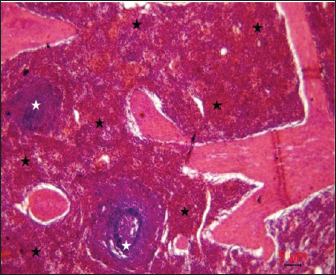

Post-mortem examinations of the dead horses infected with M. haemofelis revealed signs of overall emaciation in the affected animals, paleness of internal organs (Fig. 5), and prominent splenomegaly. The liver, kidneys were enlarged; however, the heart showed white patches. Moreover, histopathological changes were characterized by different histopathological changes of eosinophilic degeneration of cardiac muscle fibers, accompanied by atrophy in some fibers, with bleeding between fibers, besides atrophic glomeruli, accompanied with the dilatation of renal tubules in the kidneys, as well as marked reduction in the proportion of white pulp of splenic tissue and degenerative changes in the cytoplasm of hepatocytes, accompanied by nuclear alterations characterized by loss of chromatin content in the hepatic tissue (Figs. 69).

Fig. 8. Histopathological evaluation of the spleen showed a marked reduction in the proportion of white pulp (white asterisk) relative to red pulp (black asterisk), H&E,4x. Scale bar=5µm.

Fig. 9. sections demonstrated degenerative changes in the cytoplasm of hepatocytes (arrows), accompanied by nuclear alterations characterized by loss of chromatin content (arrowhead), H&E, 40x. Scale bar=5µm.